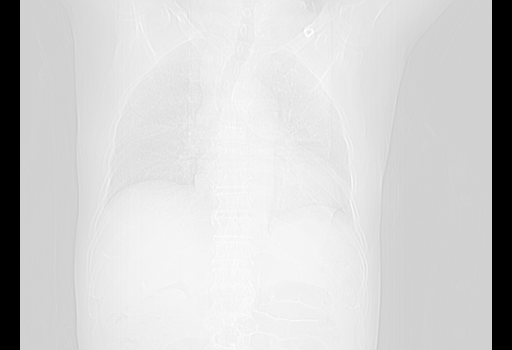

甲强龙80mg/日+抗结核治疗(异烟肼+利福霉素+乙胺丁醇)10天。复查肺部CT。

治疗10天肺部CT